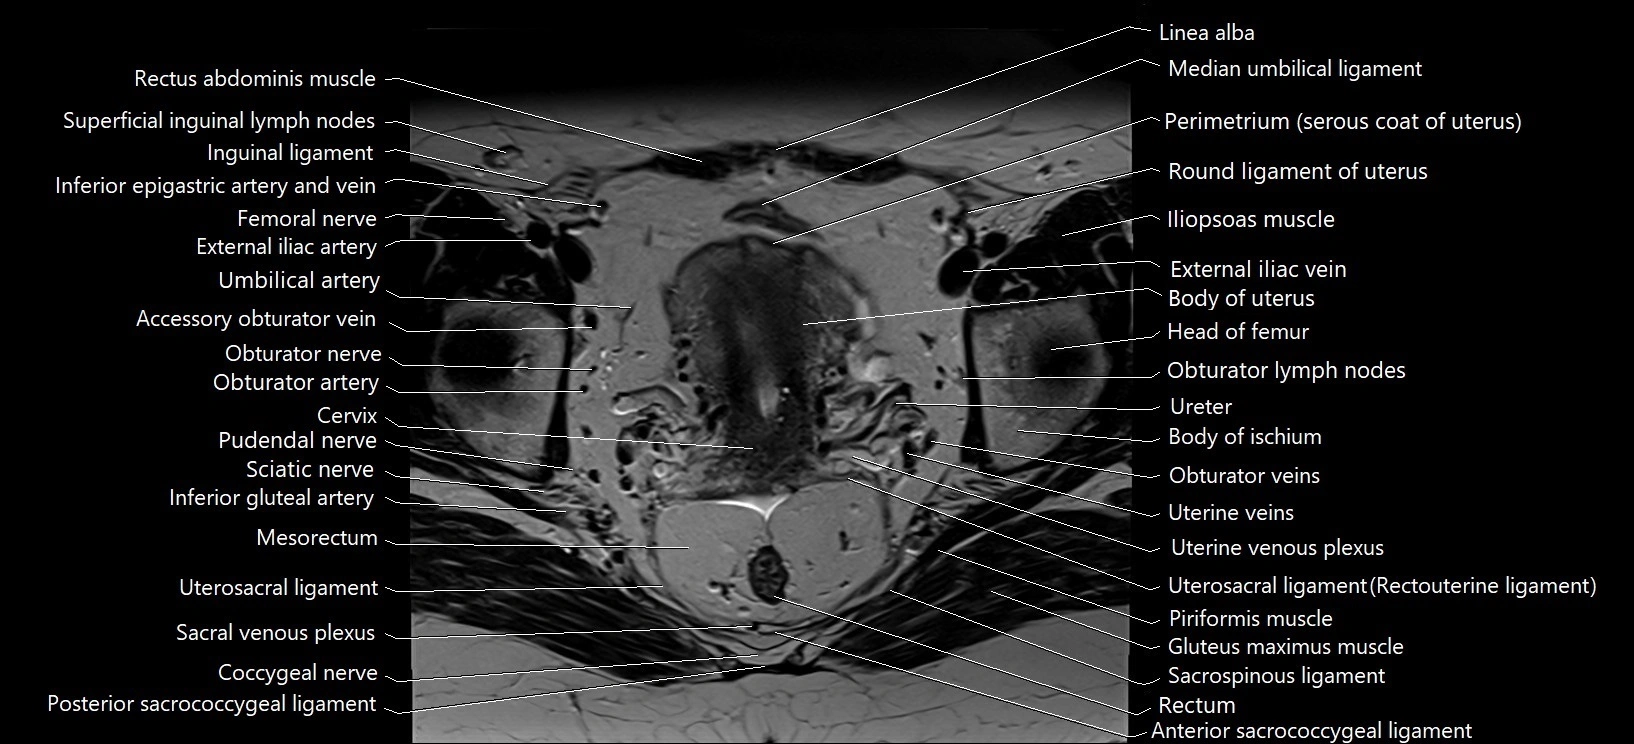

- Body of ischium

- Body of uterus

- Cervix of uterus

- Coccygeal nerve

- External iliac vein

- Iliopsoas muscle

- Median umbilical ligament

- Mesorectum

- Obturator lymph nodes

- Obturator nerve

- Obturator veins

- Perimetrium of uterus

- Piriformis muscle

- Pudendal nerve

- Rectum

- Round ligament of uterus

- Sacrospinous ligament

- Sciatic nerve

- Superficial inguinal lymph nodes

- Umbilical artery

- Uterine veins

- Uterine venous plexus

- Uterosacral ligament